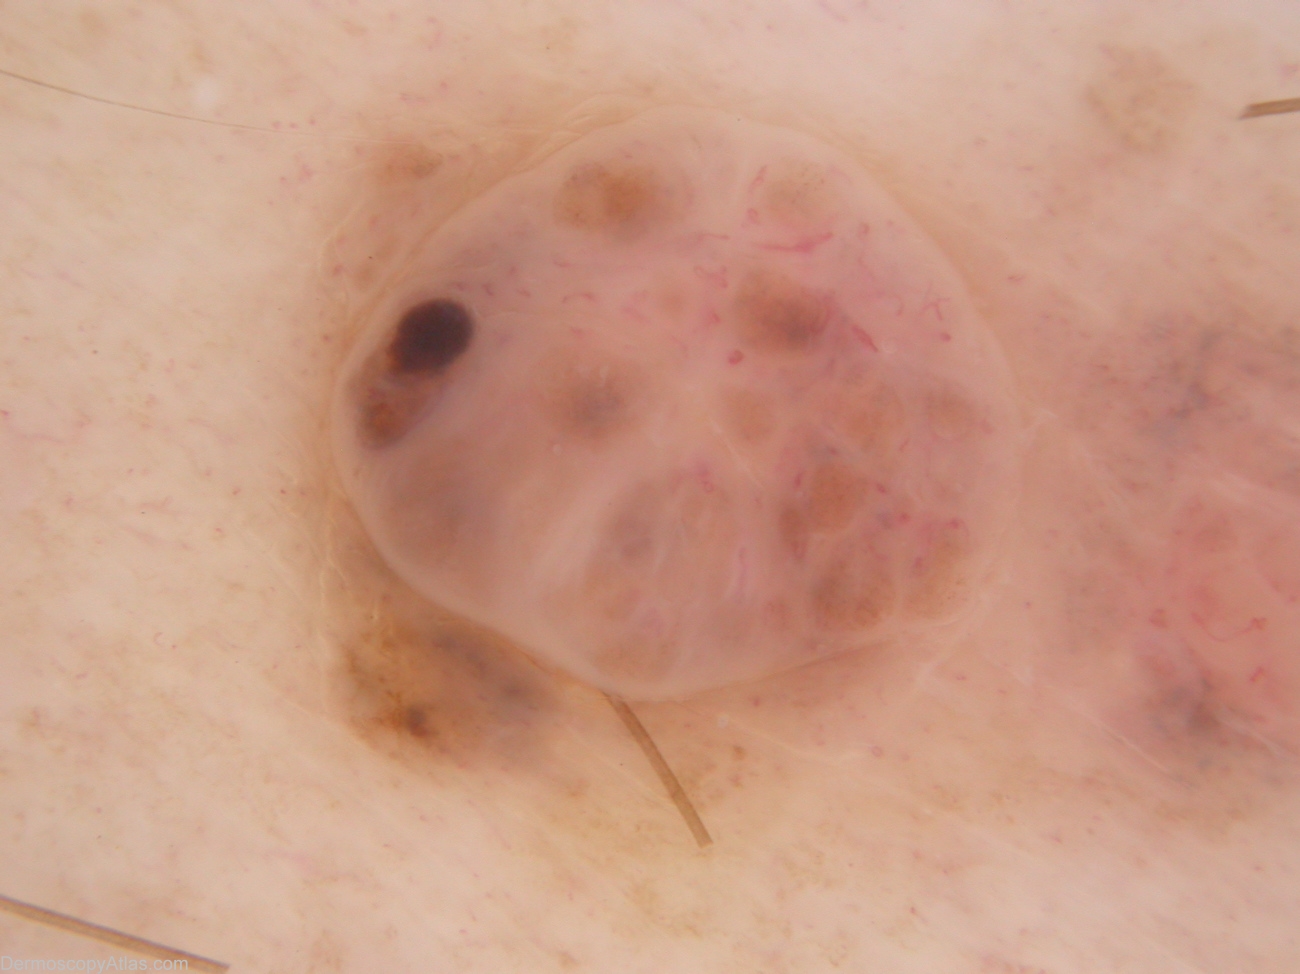

Description: The nodular component is not unlike a benign dermal naevus with maybe (in retrospect) more variability in vessel morphology and the unusual solitary brown clod. The macular component shows dots grey and more unusual fine hairpin vessels. Thes features suggest a (symptomatic) regressing melanocytic lesion.

History: 35 year old male with atypical mole syndrome. This lesion noted at examination prompted by melanoma 393. On asking, the patient mentioned this lesion had been irritated by clothing when active for the last 6-9 months. Histology reported as: Sections show a level 3 (0.8mm thick) nodular melanoma with prominent old regression. There is no ulceration, dermal mitoses or lymphocytic infiltrate.